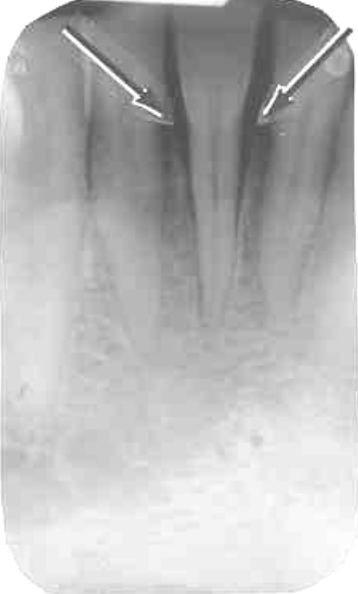

2. What is the anatomical structure indicated by arrow in this radiograph?